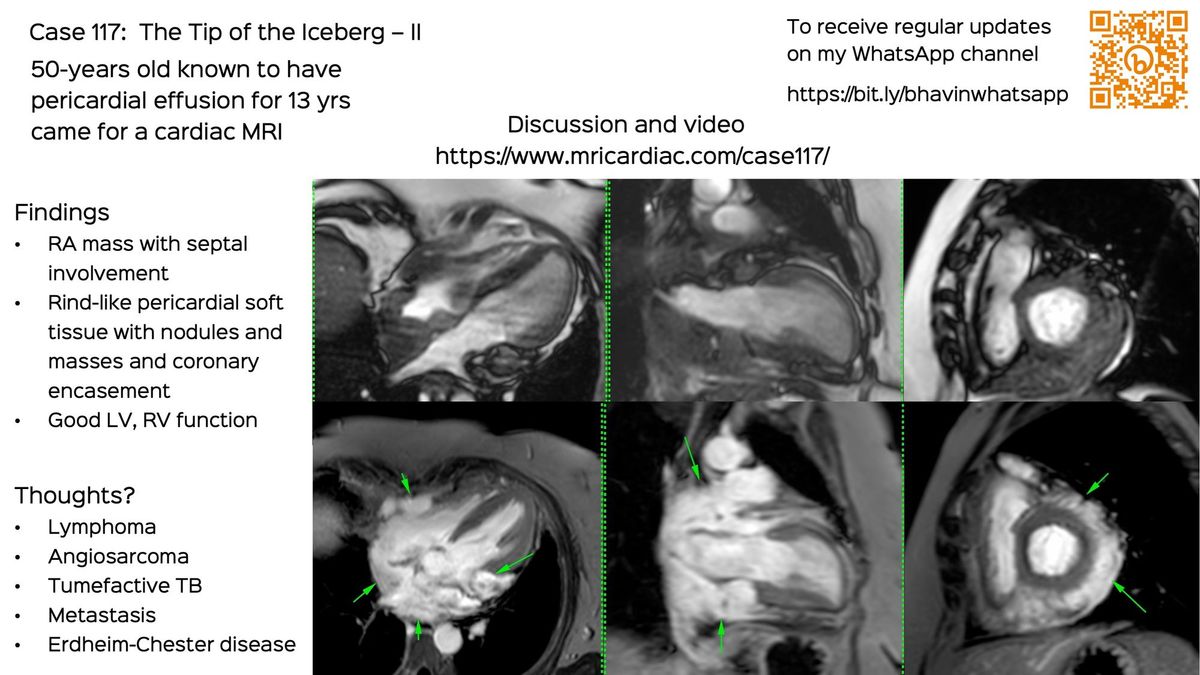

Case 117: The Tip of the Iceberg - II

Today's case is about a 50-years old patient with pericardial effusion for 13 years, who came for a cardiac MRI, which showed a right atrial and interatrial septal mass with pericardial soft tissue and coronary artery encasement.

This led to a PET/CT and a biopsy and an unusual diagnosis.